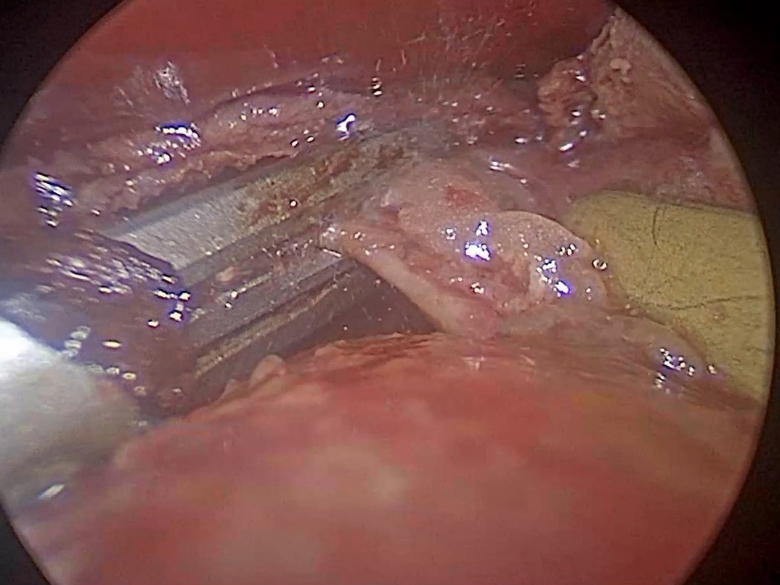

術中の様子。

術中のカメラ映像。超音波凝固切開装置を用いて心膜を処理しているすぐ下に動く心臓がある。

切除した心膜